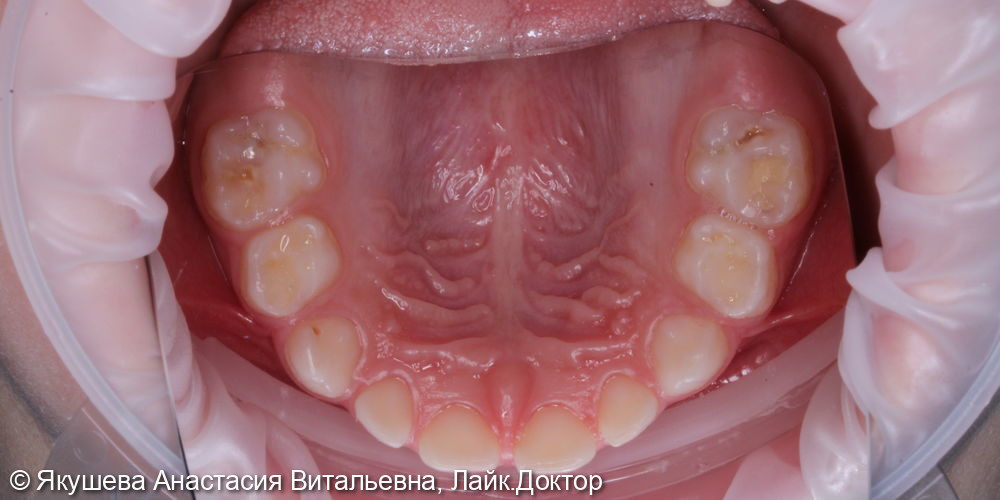

55;54;64;85;84;74;75 : К04.0 Пульпит (K04.0 Пульпит)

53;51 - 63;65;83;73 : К02.1 Кариес дентина (K02.1 Кариес дентина)

55;53;65;74 : в условиях общего обезболивания очищение мягкого зубного налета, изоляция коффердам, проведено препарирование кариозной (ых) полости (ей), под контролем витального окрашивания «Кариес Маркер» удалены деминерализованные участки эмали и дентина, формирование кариозной полости антисептическая обработка раствором хлоргексидина 2%,Показать полностью...